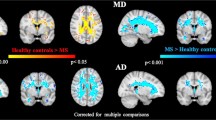

Compared to HC, MS patients showed significant regional GM loss in the following areas: the thalamus, bilaterally; the postcentral gyrus, bilaterally; the right precentral gyrus; the right inferior temporal gyrus; the insular cortex, bilaterally; the middle temporal gyrus, bilaterally; the left superior frontal gyrus; the right cerebellum; the left pallidum; the left cingulate gyrus; the right putamen; the right temporal pole and the left inferior frontal gyrus (Fig. 2, Table 3). No areas of regional GM volume reduction were found in HC when compared to MS patients.

Regional pattern of gray matter (GM) atrophy in patients with multiple sclerosis (MS), compared to healthy controls (HC), superimposed on the customized GM template. Legend: The regions of significant reduced GM volume in MS patients (p < 0.05) are shown in red-yellow (t-value 0–8). Abbreviations: A = anterior, P = posterior, L = left, R = right, S = superior, I = inferior

To assess whether GM regions showing correlations with SDMT performance are also atrophic in MS patients, a whole-brain VBM analysis comparing MS patients and HC was also performed. Our findings are in line with those of previous studies (Prinster et al. 2006; Lansley et al. 2013) reporting regional GM loss at the level of the thalamus, basal ganglia, pre/postcentral and cingulate gyri in MS patients (Lansley et al. 2013). Interestingly, in our study, all SDMT-correlated GM regions, except for occipital cortex, were atrophic in MS patients.